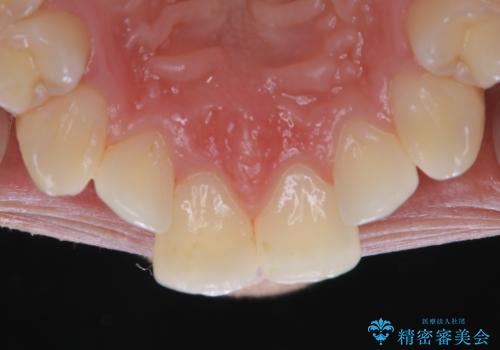

- iTeroスキャン(インビザラインの型どり)をより綺麗にスキャンしたいとのことでした。PMTC(自費クリーニング)30分コースを行い、歯の汚れやステインを取り除きました。

インビザラインの型どりの前に、プラークやステインを除去することで綺麗なスキャニングが行えます。より精度のよいマウスピースを作成するために、PMTCを行うことをおすすめしています。